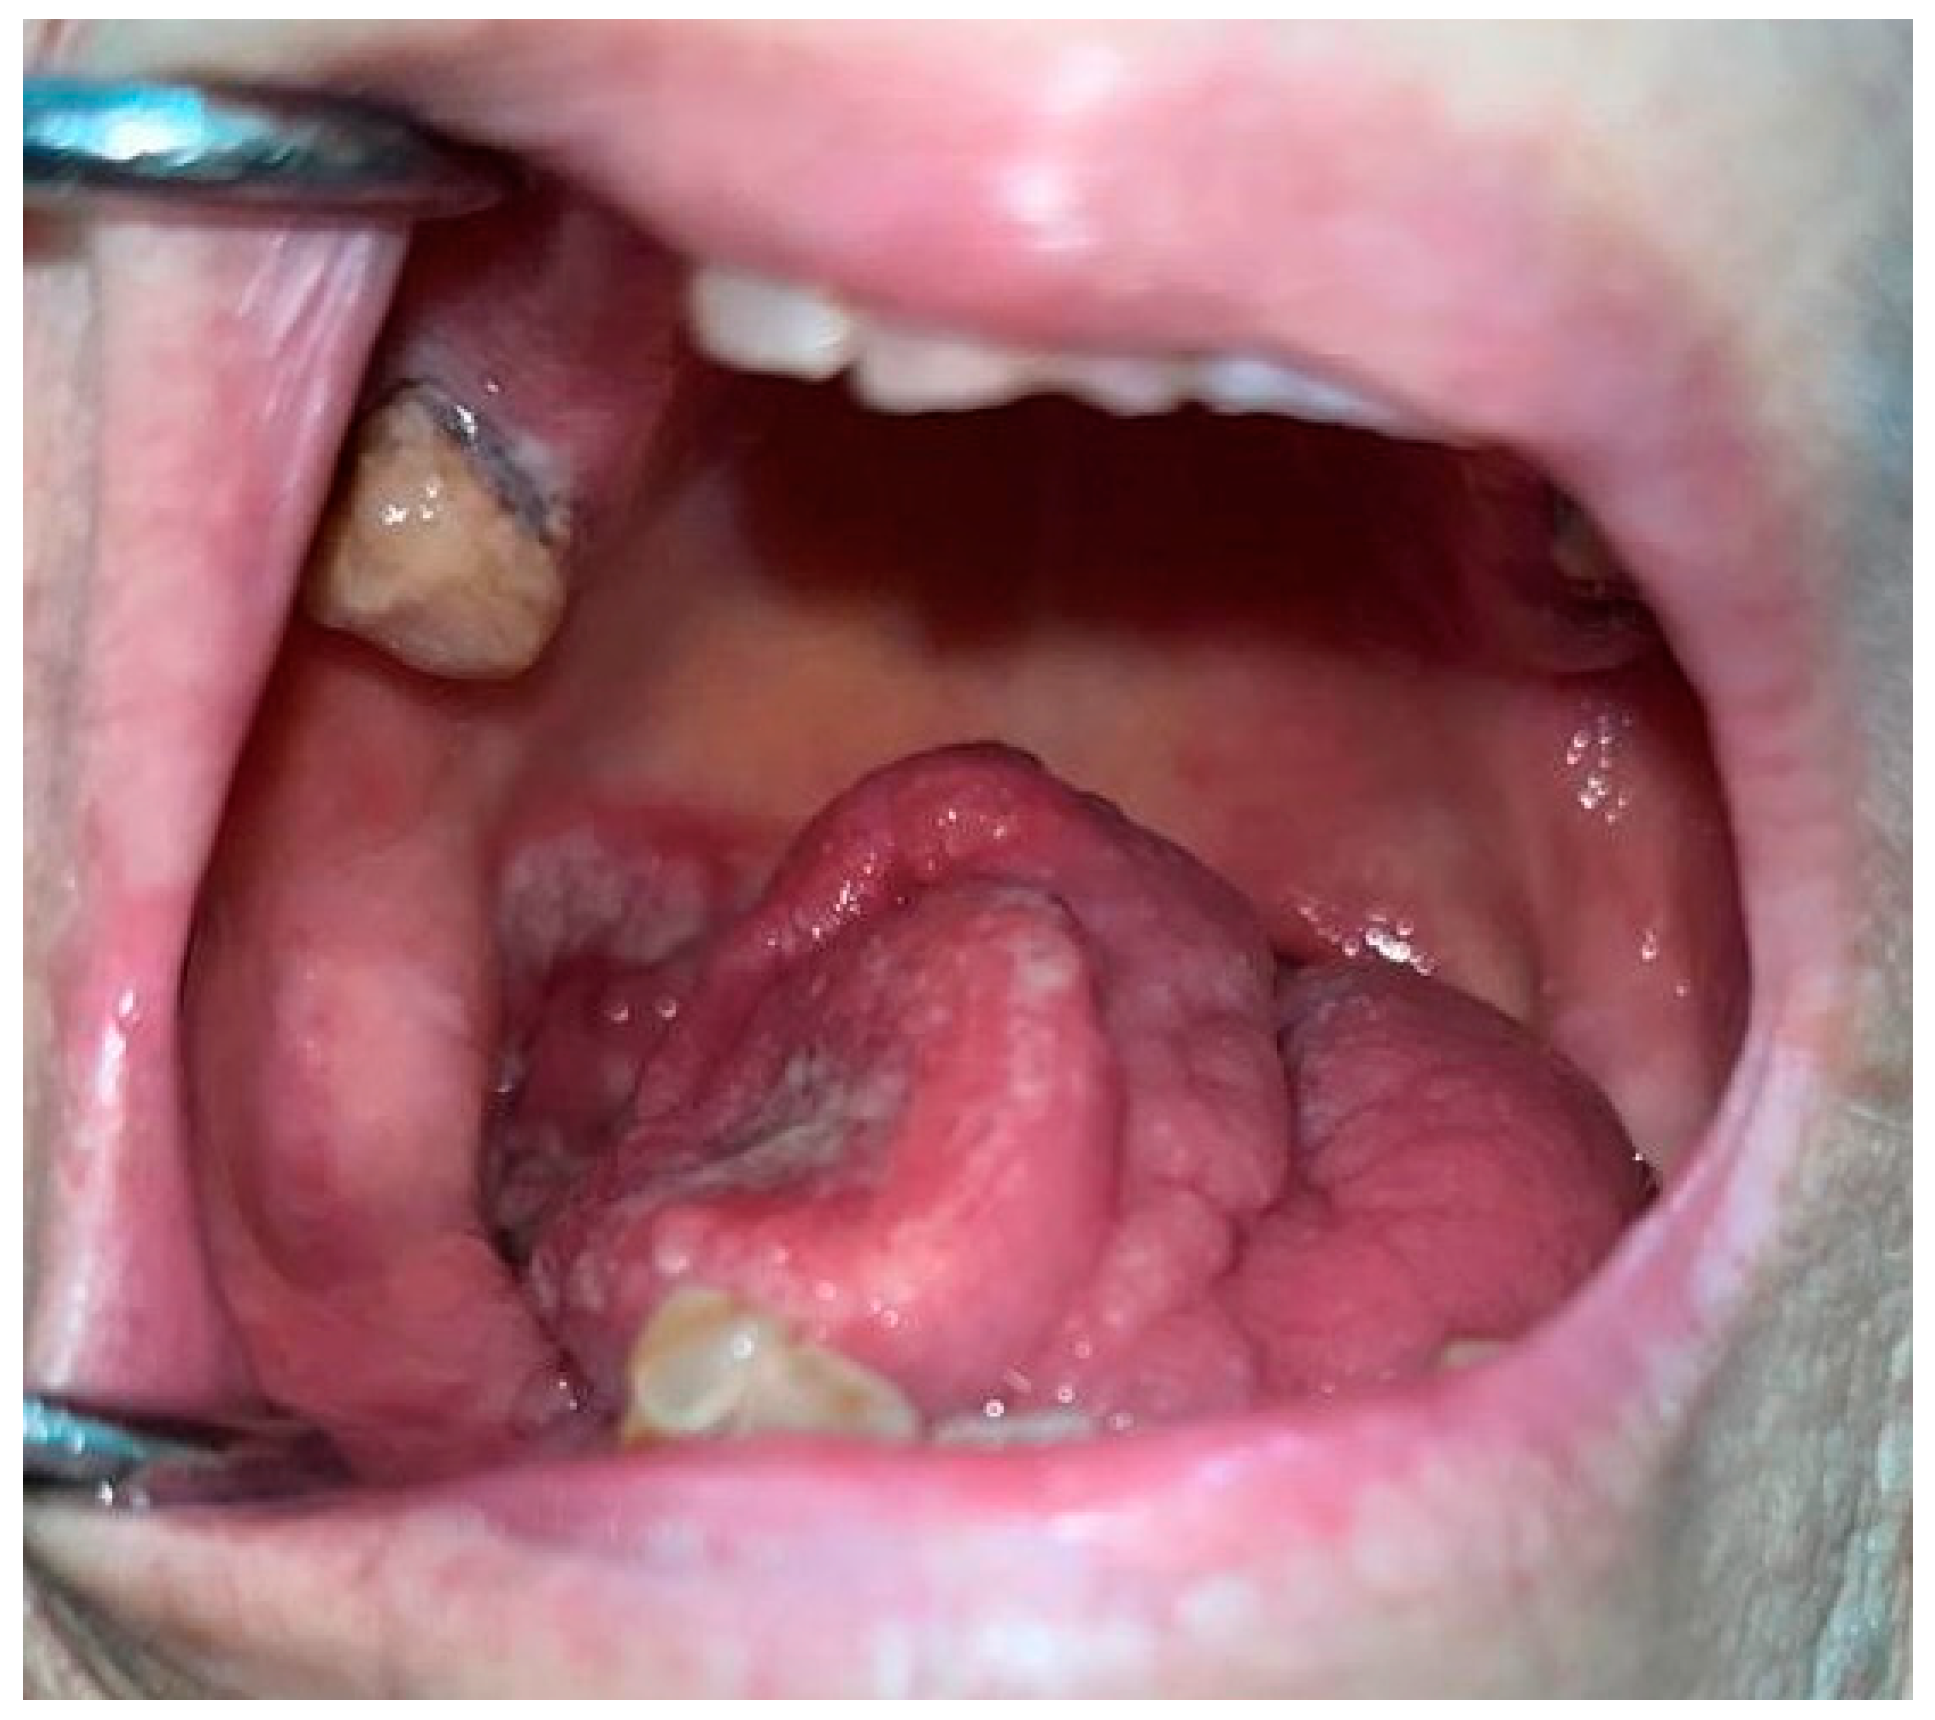

2.1. Oral Leukoplakia, Proliferative Verrucous Leukoplakia and Erythroplakia

3. Oral Malignancies